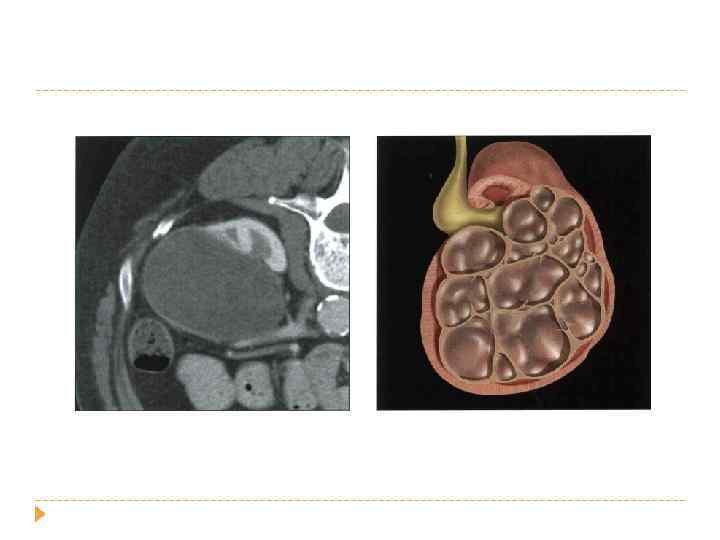

наследственный поликистоз у детей

наследственный поликистоз у взрослых 1: 1000 населения в год почки могут быть до 40 см и весить 8 кг ОСЛОЖНЕНИЯ : артериальная гипертензия (60%) пиелонефрит нефролитиаз

ПОЛИКИСТОЗ Сочетание поликистоза печени и почек